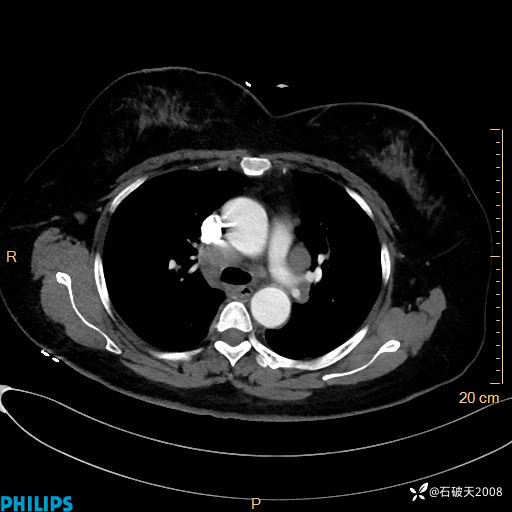

肺结节病?纵膈型肺癌?淋巴瘤?有点意思,欢迎围观

女 52岁 主 诉:咳嗽10余天,咳痰2天。

现病史:10余天前无明显诱因出现咳嗽,呈阵发性干咳,伴咽喉部发痒,无咽痛,无咳痰,无鼻塞、流涕、打喷嚏,无发热、畏寒、寒颤,无头痛、头晕,无胸闷、胸痛,无反酸、烧心,无腹痛、腹泻,无尿频、尿急,无皮疹等,在当地诊所求治,给予口服药物治疗(具体不详),病情无好转。遂在当地社区卫生服务中心开具口服药物治疗(具体不详),疗效欠佳。2天前出现咳痰,在我院门诊求治,行胸部CT提示肺部感染,建议住院,患者要求口服药物治疗,目前仍咳嗽、咳白色粘痰,白天量多,夜间自觉喉部喘鸣音,遂再次来院就诊,以“肺部感染”为诊断收入院。发病以来,神志清,精神可,饮食可,夜间睡眠差,大小便正常,近期体重无明显变化。

动脉期